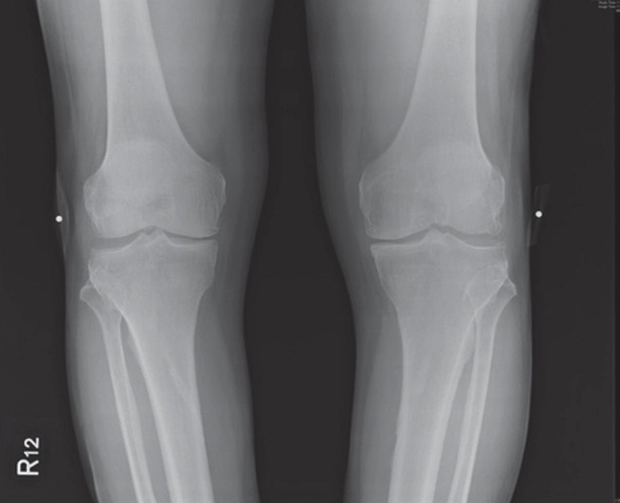

圖/手術後一年。

ACRFP術後滿一年的X光片,關節間隙變寬,有明顯改善。我們對這結果都非常滿意。一年來,吳先生未曾服藥,如果能繼續做適當的保健,原本需要置換人工關節的膝關節,應可逐年改善。又是一個「軟骨能自然修復」的見證!